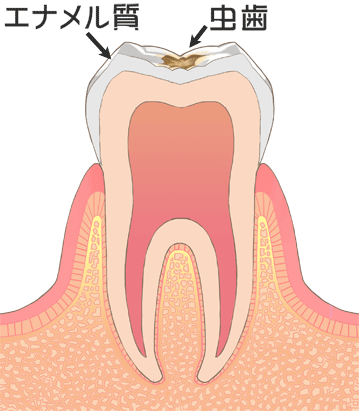

⑥ 前回詰めた綿花の状態を確認して、良い状態なら、「根管充填剤」(マスターポイント・アクセサリーポイント)というお薬を、余分な空間がないように根っこに詰めます。

⑥ 前回詰めた綿花の状態を確認して、良い状態なら、「根管充填剤」(マスターポイント・アクセサリーポイント)というお薬を、余分な空間がないように根っこに詰めます。 Q1.痛みはありますか?

Q1.痛みはありますか? ② 次に、「根管長測定器」という機械を使い、根っこの長さを正確に測ります。

② 次に、「根管長測定器」という機械を使い、根っこの長さを正確に測ります。

⑤ 次に、仮詰めをします。

⑤ 次に、仮詰めをします。 虫歯が神経まで達して炎症を起こしているので、人によってはズキズキとした痛みを感じる方もいます(>_<)

虫歯が神経まで達して炎症を起こしているので、人によってはズキズキとした痛みを感じる方もいます(>_<)